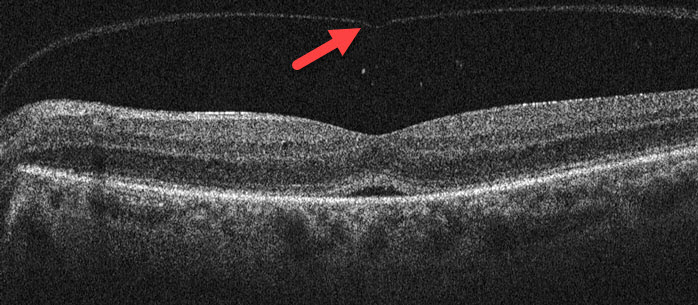

Throughout life the vitreous (the gel-like substance inside the eye) normally liquefies and gradually separates from the retinal surface. Although this usually results in a complete separation of the vitreous (posterior vitreous detachment), it can sometimes remain stuck to the central macula, the specialized area of the retina that gives us our straight-ahead reading and driving vision. Vitreomacular traction occurs when the adherent vitreous tugs and distorts the macula.

You can’t diagnose vitreomacular traction by looking in the mirror since your eye will look and feel normal. The diagnosis is made with a thorough retinal examination through a dilated pupil and confirmed with OCT scanning.